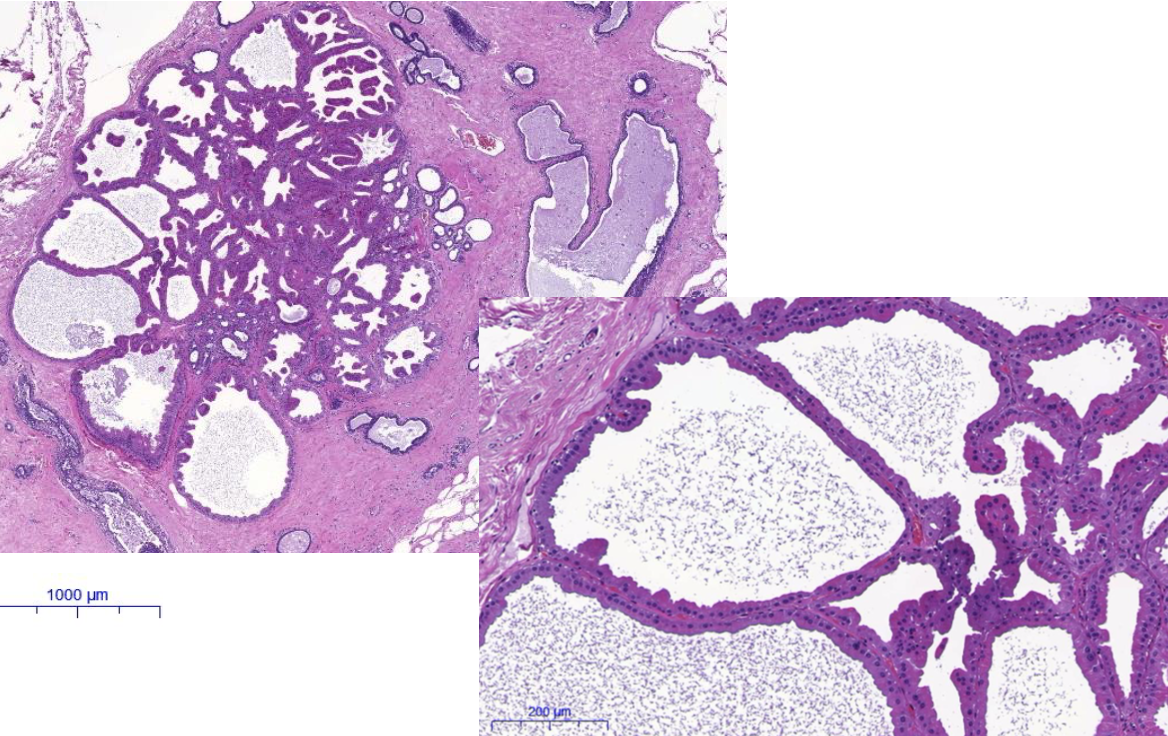

Diagnose?

Fibroadenom